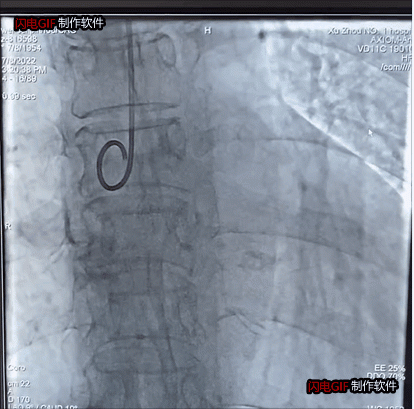

瓣膜植入前主動(dòng)脈瓣大量反流

瓣膜植入后反流完全消失

整個(gè)手術(shù)過(guò)程僅1小時(shí),瓣膜釋放后主動(dòng)脈瓣反流完全消失,舒張壓迅速由14上升到60mmHg左右。目前患者已順利康復(fù)出院。